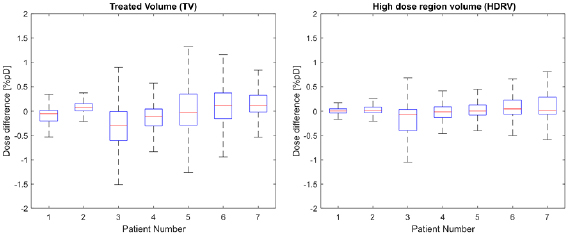

Standard image High-resolution imageThe results of the voxelwise dose difference analysis for the two selected regions are presented at figure 7.

Figure 7. Boxplots showing the distribution of voxelwise dose differences for each patient for the TV (treated volume—region exceeding 95% of the prescribed dose) and the HDRV (high dose region volume—region exceeding 50% but less than 95% of the prescribed dose). Outliers corresponding to points outside the ±2.7 s.d. range have been suppressed.

Download figure:

Standard image High-resolution imageDosimetric validation—DVH data